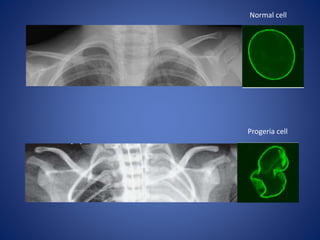

Normal cell

Progeria cell

What is thecause of Progeria? HGPS is caused by a mutation in the gene called LMNA (pronounced “lamin-a”). The LMNA gene produces the lamin A protein which is the structural scaffolding that holds the nucleus of a cell together. The abnormal lamin A protein that causes Progeria is called progerin. Progerin makes the nucleus unstable. That cellular instability leads to the process of premature aging and disease in Progeria.